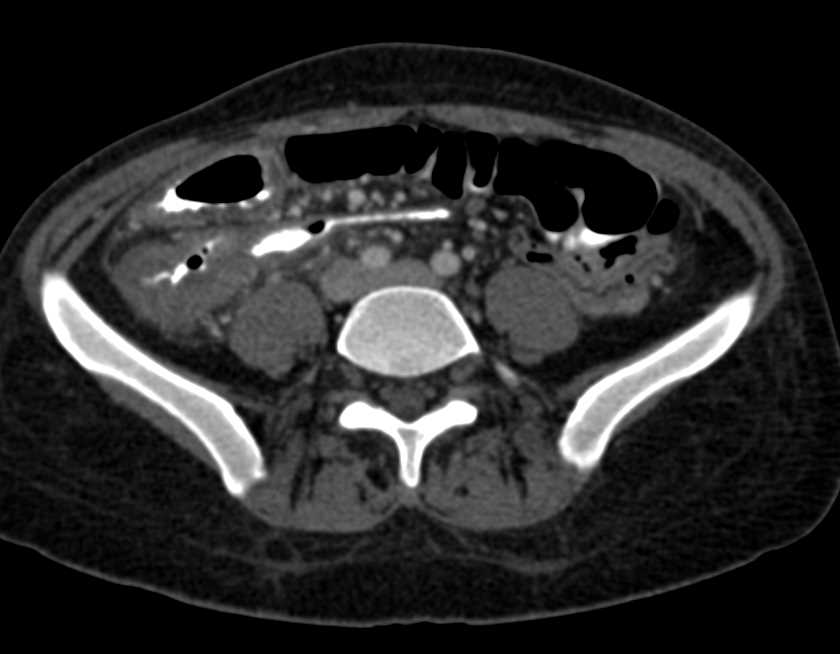

Perforated Rectum with Extensive Air Around the Rectum